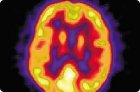

別の方法

MRIは、脳のCTを行う代わりに使用することができる。情報を少なくしても、部分的にCTを置き換えることができます。

脳のCTスキャンの精神障害の「有機」の方法で可視化萎縮性脳病変と一緒に精神科クリニックでは、統合失調症における構造異常や他のいくつかの「機能」とは、障害の機能の数を明らかにしました。例えば、統合失調症患者は、しばしば体積または部分的萎縮を増加させる、萎縮小脳及びより顕著な破壊前頭前皮質の存在が他の皮質領域に比べて、(「陰性」症状の存在および最悪効率神経弛緩薬治療と組み合わされる)拡張横方向および第三脳室を明らかにする脳梁、他の精神病患者と健常者で指摘されていない右半球の優位性と形態学的な脳の非対称性。